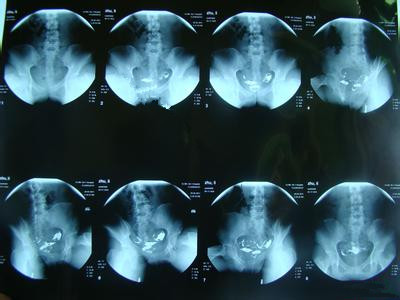

子宫输卵管造影检查(HSG)是指通过导管向宫腔及输卵管注入造影剂,行X线透视及摄片,根据造影剂在输卵管及盆腔内的显影情况了解输卵管是否通畅、堵塞部位及宫腔形态。输卵管造影检查损伤小,能对输卵管堵塞做出较正确诊断,准确率达80%,且具有一定的治疗作用。》》》子宫输卵管造影的费用是多少呢?

检查开始前,患者脱去一个裤腿上的裤子,仰卧于操作台上,双腿屈曲外展,充分暴露外阴,再由妇科护士为患者常规消毒外阴、阴道,铺无菌巾,检查子宫位置及大小。然后用窥阴器扩张阴道,充分暴露宫颈,再次消毒宫颈及阴道穹窿,用宫颈钳钳夹宫颈前唇,探查宫腔。最后将造影剂充满导管,排尽空气,将导管插入子宫颈,堵紧宫颈外口,防止造影剂外溢。推注造影剂并在X线透视下观察造影剂流经子宫腔及输卵管的情况并摄片。

●若输卵管通畅,则表现为子宫充盈呈倒三角形,两侧输卵管像细导管弯曲在子宫两侧,造影剂先充盈输卵管近端的峡部,然后迅速向壶腹部充盈,继而自伞端弥散至盆腔。

●若输卵管阻塞,则表现为输卵管完全不显影或显影一段后不再显影,且造影剂注入到一定剂量时阻力加大,盆腔内无造影剂弥散。

●若输卵管通而不畅,则表现为推注造影剂有阻力,造影剂进入盆腔缓慢。在停住造影剂数十分钟后,可见造影剂在盆腔内弥散,但弥散欠佳。

●若输卵管积水,则表现为造影剂积聚在输卵管内,输卵管异常扩张且呈囊状或腊肠状,以远端明显,多伴有输卵管阻塞。盆腔内一般无造影剂弥散。

●若输卵管伞端周围粘连,则表现为造影剂可以进入腹腔,但积聚在输卵管伞端周围,弥散不佳。